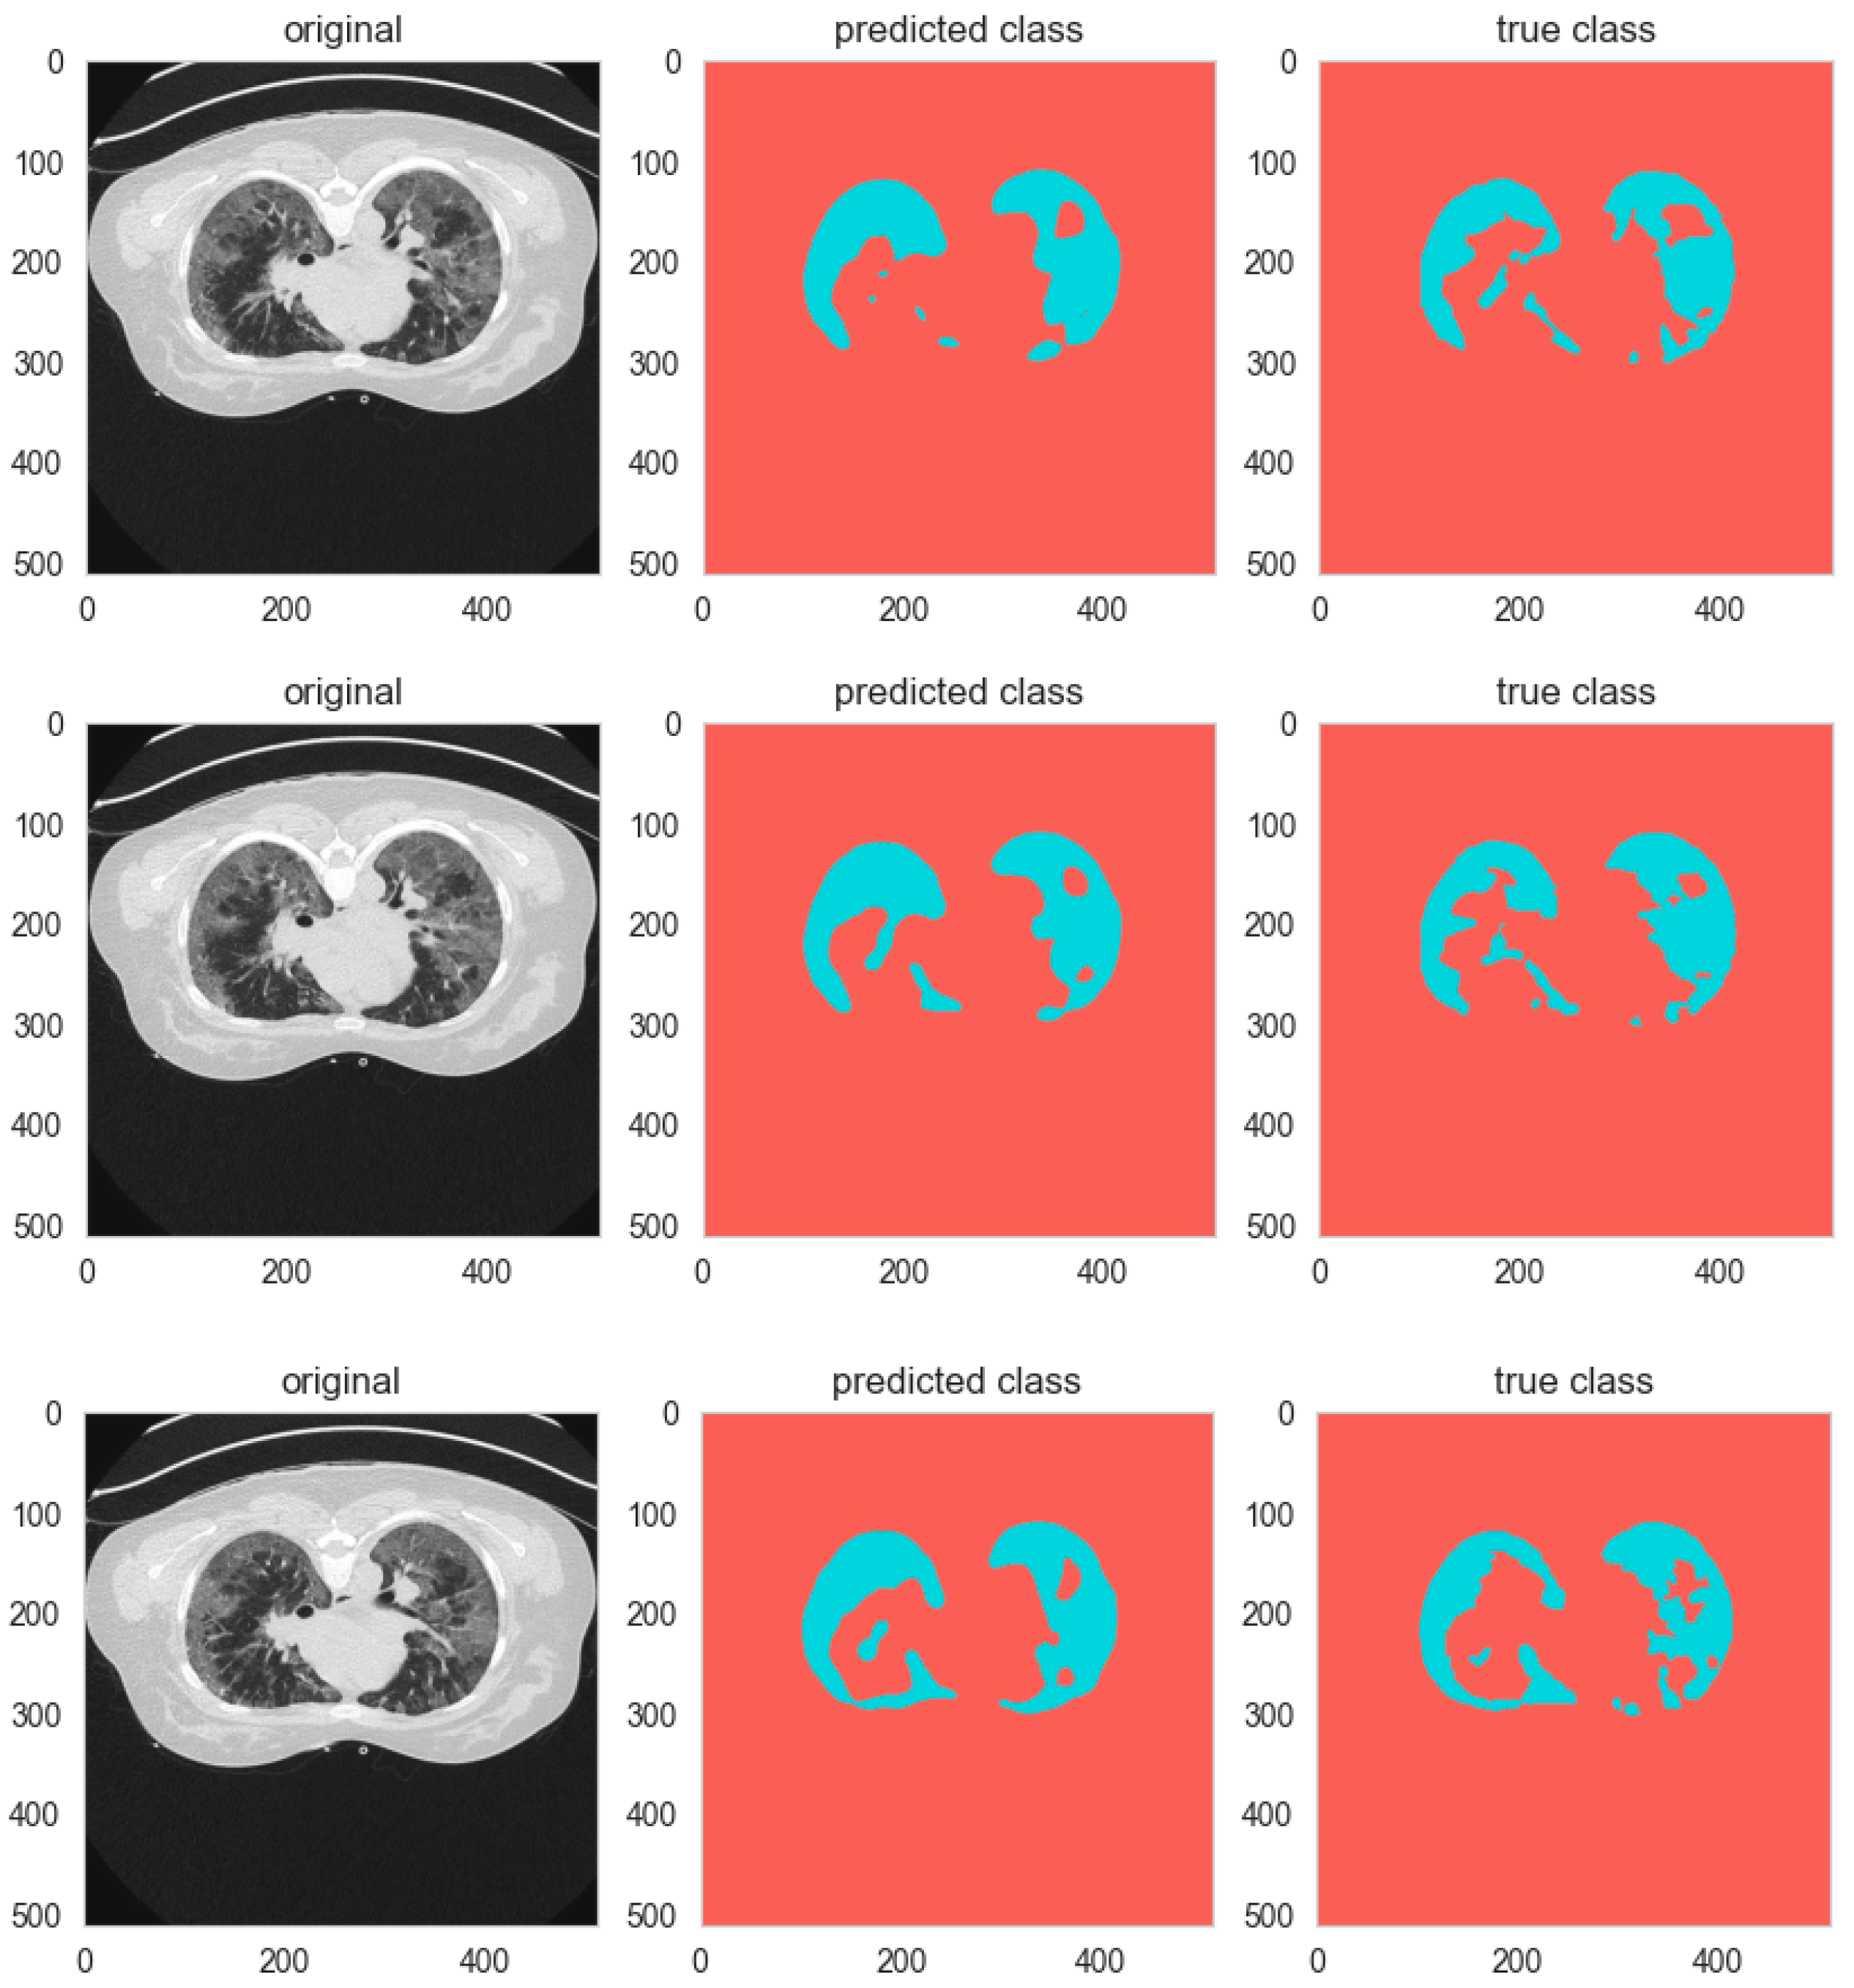

The analysis is worth deeper investigation; Specificity, also called the true negative rate, assesses the performance of the model to identify background pixels, while Sensitivity, also known as the true positive rate, measures its ability to identify foreground objects. Both measures improve as the number of groups increases. For the 2-group Channel-wise shuffle setup, Sensitivity and Specificity are at 0.963 and 0.94, respectively. When we move to the 4-group Channel-wise shuffle, the values are 0.97 and 0.945. However, the top one among these is the 8-group Spatial-wise shuffle model, which has a Sensitivity of 0.9757 and Specificity of 0.9532. These higher values indicate the manner in which the use of additional groups and the Spatial-wise shuffle technique assist the model in segmenting foreground objects and categorizing background pixels more effectively. Figure 7 shows samples of Group and Shuffle results.

Figure 7. Sample of group and shuffle segmentation outputs.